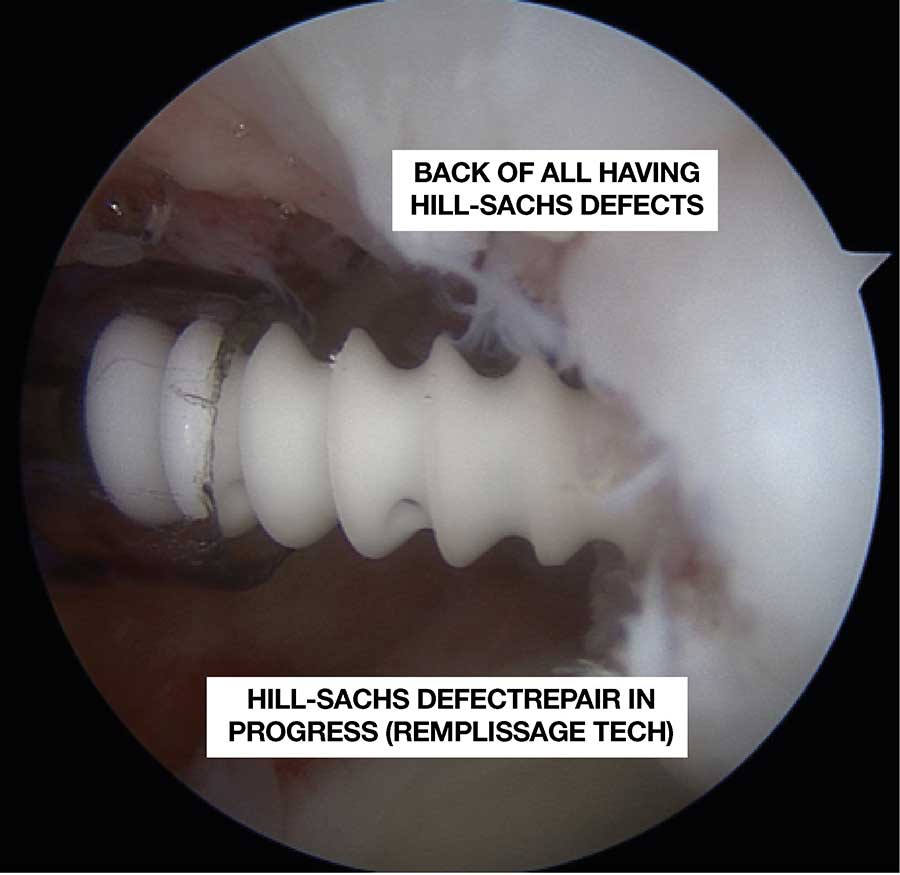

Sometimes, the defect in the ball of the shoulder is large so that it becomes wider than the socket!! In such scenarios, we need to do Bankart repair and in addition we fill the defect (French word Remplissage) with Muscle at the back of the shoulder. This is done all by key-hole surgery.